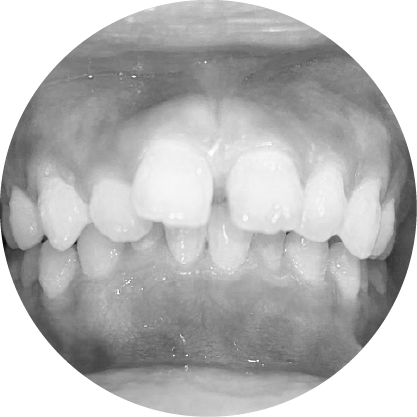

ฟันเกคือภาวะที่ขากรรไกรมีพื้นที่ไม่เพียงพอ ทำให้ฟันซ้อนหรือเรียงตัวไม่เป็นระเบียบ การรักษาช่วยเพิ่มพื้นที่เพื่อจัดฟันให้เข้าที่อย่างเหมาะสม ส่งผลให้รอยยิ้มดูสวยงามขึ้นและสุขภาพช่องปากดีขึ้นด้วย

ตัวอย่างในชีวิตจริง